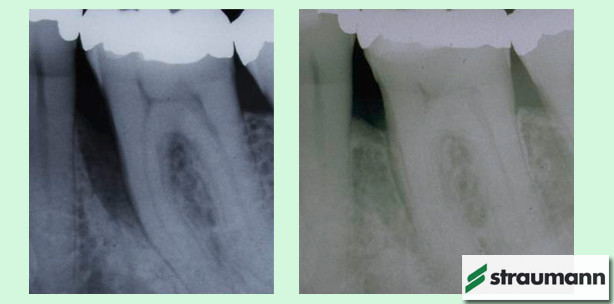

Foto: © Straumann

Wissenschaftliche Studien zu Straumann Emdogain

Dr. Frank Bröseler, Aachen, und Birgit Sayn, ZMV, Leverkusen, stellen ein Therapiekonzept vor, das laut Straumann zugleich medizinischen und wirtschaftlichen Ansprüchen genügen soll. Daran anschließend befasst sich Professor Holger Jentsch, Leipzig, in seinem Vortrag mit der aktuellen Studienlage zu Straumann Emdogain und erörtert eine mögliche Anwendung in Fällen mit horizontalem Knochenabbau. Der Nachmittag endet mit dem Referat von Dr. Christoph Hardt, München, der Fälle aus seiner langjährigen Praxis zeigt. Danach ist eine Diskussion mit den Teilnehmern über Therapieoptionen anhand praktischer Beispiele aus der Regeneration mit Schmelzproteinen geplant.